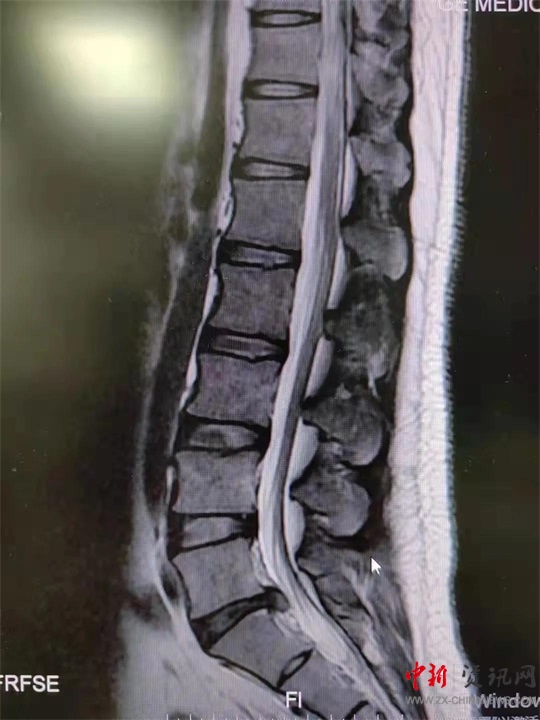

9月初,盧先生來到駐馬店市第一人民醫(yī)院就診。影像學(xué)檢查提示腰5骶1椎間盤突出。患者癥狀、體征與影像學(xué)表現(xiàn)相符,腰椎間盤突出癥診斷明確。結(jié)合患者情況,蔣學(xué)國主任團(tuán)隊(duì)決定舍棄傳統(tǒng)手術(shù)方案,為患者實(shí)施UBE技術(shù)下腰椎間盤髓核摘除術(shù),這也是UBE技術(shù)在西院區(qū)的首次應(yīng)用。